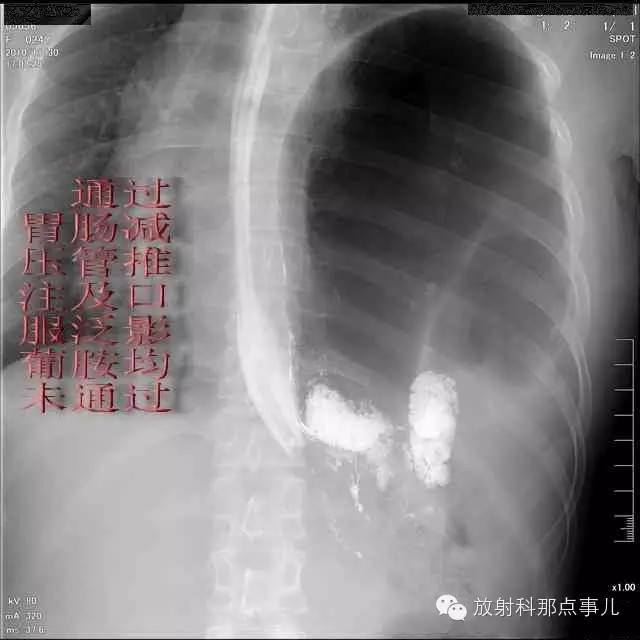

门诊腹部透视发现左侧胸腔巨大气液平面,为排除膈疝口服钡剂,但造影剂未见进入胃内。嘱住院,外科给予胃肠减压、补液等处理常规处理(未引流出明显气、液体)。5个半小时后再次检查,见少量造影剂进入消化道;为进一步了解情况,予泛影葡胺分别经胃管推注及口服,但均未进入胃内。当天进行外科急诊手术。

更正:检查时间在左上方。